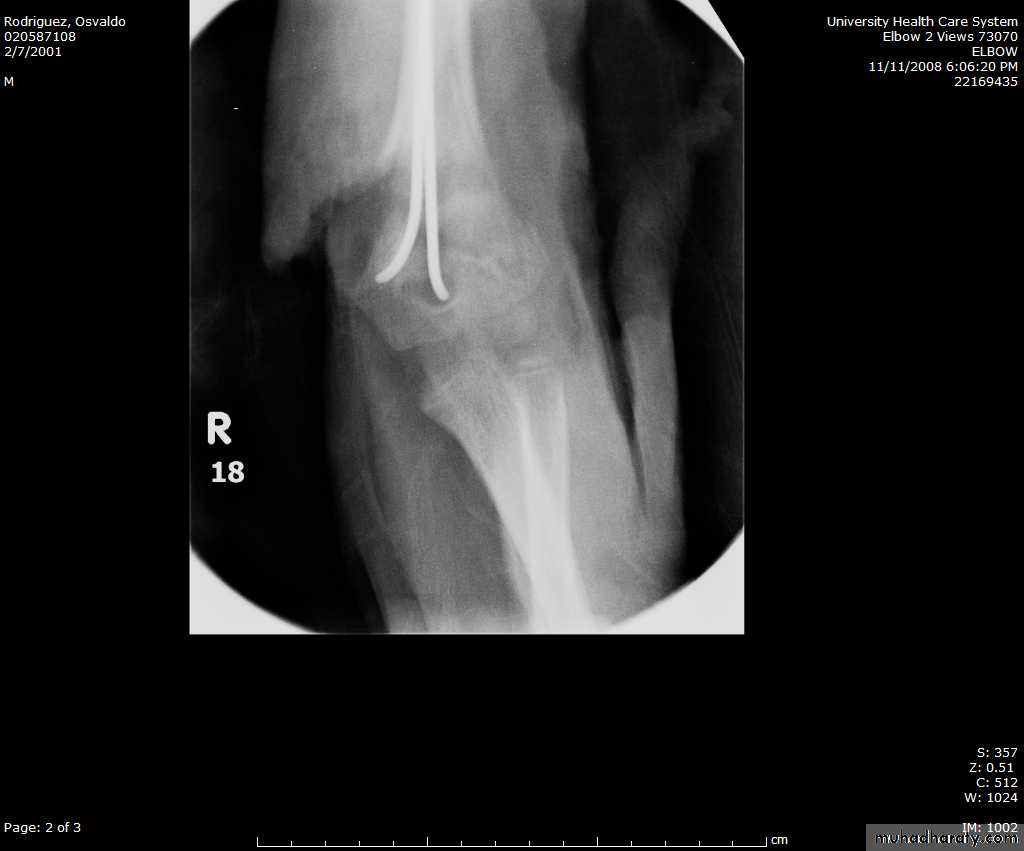

How are we going to stabilize this boy’s fracture?

This is probably one of the few indication to use

Antegrade Flexible I M NailsOur Patient P.O.

Probably acts more

as an internal splintSix months post-operative

How is he doing clinically?